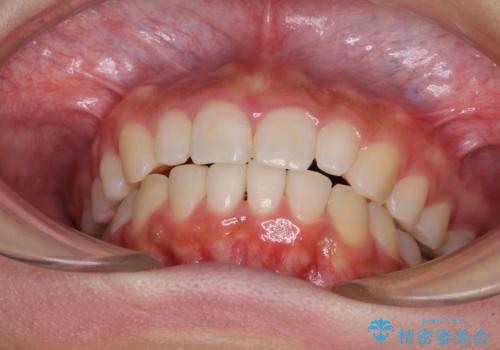

上顎左右前歯に矮小歯があるため、上顎の奥歯は下顎に対して相対的に前方に位置することになりました。

それでも奥歯の咬みにくさはなく、患者様には大変満足していただきました。